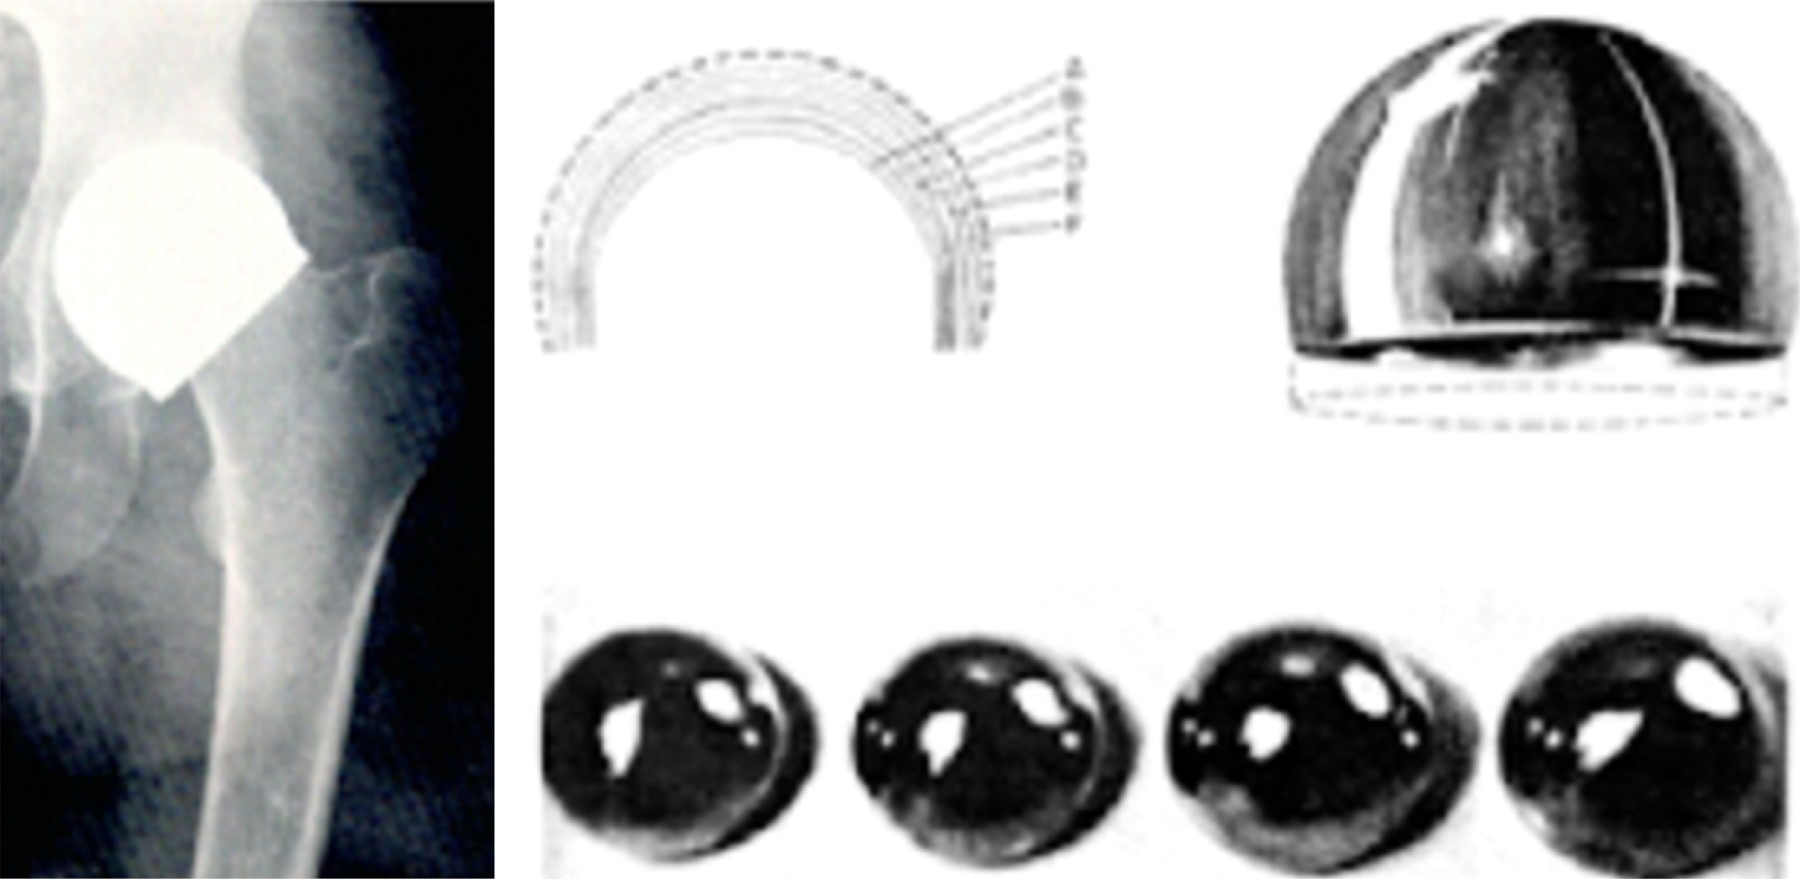

Fue hasta 1970 cuando el Dr. Marco Antonio Lazcano, entonces alumno del Dr. Charnley, colocó la primera prótesis de cadera cementada en el Centro Médico ABC, así como en el Instituto Nacional de la Nutrición, de aquí fue seguido por varios cirujanos ortopedistas, siendo este implante uno de los más utilizados en los años 70 y 80 en nuestro hospital, debido a la rápida fijación de los implantes con el invento del maestro Charnley, el cemento de hueso (polimetilmetacrilato [PMMA]), mismo conocimiento que plasmó en 1984 en el libro llamado Artroplastia total de cadera tipo Charnley que mencionaba recomendaciones, técnica y conceptos importantes sobre la cadera y las prótesis de baja fricción, con el objetivo de convertir al Hospital ABC en un centro de reemplazos de Charnley, así como difundir el conocimiento a toda Latinoamérica. Esta publicación se realizó gracias a un donativo importante por parte del entonces Hospital ABC (Figura 4).1,3

En la misma época desarrolló un implante monopolar cementado basado en el diseño del vástago recto de Charnley, con el fin de facilitar el tratamiento de las fracturas de cadera intracapsulares en pacientes de tallas mexicanas. De este implante obtuvo el título de registro de modelo industrial en 1993, llamándole prótesis tipo Lazcano; más tarde le agregó al diseño un cuello con el que propuso este implante para el tratamiento de las fracturas extracapsulares, dedicándole a este implante dos libros. A la fecha, aún se produce este modelo con el concepto que entonces tenía el Dr. Lazcano, un implante de fácil colocación, de costo accesible y buena función (Figura 7).

Algunos cirujanos, como el Dr. Holshneider y el Dr. Velutini también en los 70, prefirieron la tecnología europea colocando la prótesis cementada de Charnley-Müller, que utilizaba un vástago curvo no cementado con copa de polietileno con resultados muy similares a los de la famosa prótesis de baja fricción de Charnley. Con el fin de demostrar que este implante de cadera era confiable, el Dr. Buchholz, otro profesor de cadera ampliamente conocido por todos, fue invitado al Hospital ABC donde realizó algunas artroplastias, además de dar unas pláticas sobre la experiencia de la ENDO-Klinik de Hamburgo.